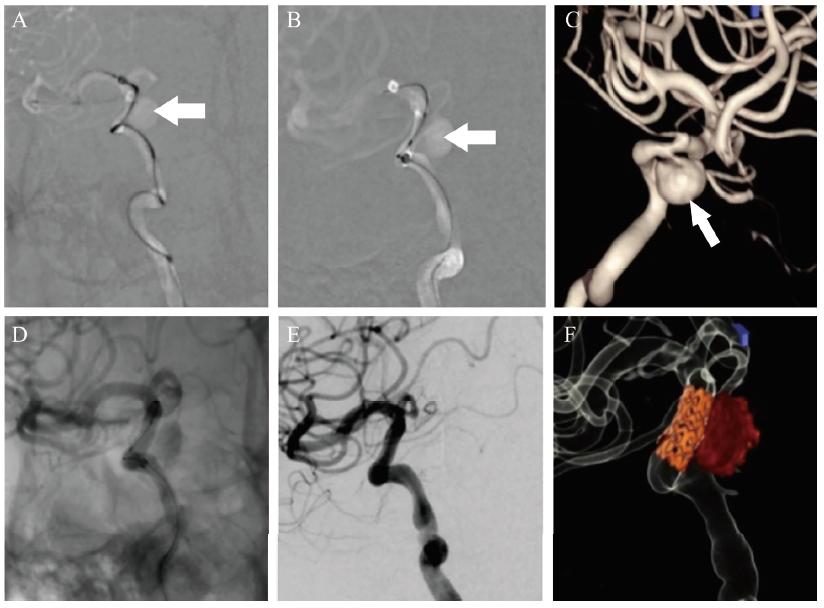

1月28日患者转入神经外科完善全脑血管造影,术中见右侧颈内动脉海绵窦段巨大动脉瘤(14.43 mm×11.34 mm)(图2),但瘤颈细小,载瘤动脉段欠平直,管径不均匀,瘤颈距眼动脉很近,离海绵窦段前曲也很近,选择行载瘤动脉段覆膜支架植入术(图3),患者于术后次日出院(图1B),围术期及出院后继续服用甲泼尼龙40 mg/d,硫酸羟氯喹200 mg每日2次治疗。最后诊断:①SLE、SLE血液系统损伤、狼疮肾炎、神经精神性SLE;②右侧颈内动脉海绵窦段动脉瘤;③右侧动眼神经麻痹;④双眼浆液性视网膜脱离。

图3 一例SLE伴颅内动脉瘤致右眼睑下垂患者的DSA术中及支架植入术后结果

注:A~C为DSA术中,可见颈内动脉海绵窦段动脉瘤(箭头所示);D~F为支架植入术后动脉瘤不再显影。